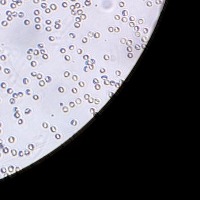

RBC Platelet v1 Computer Vision Project

Medical Diagnostic Tools: "RBC Platelet v1" can be integrated into diagnostic software systems to help physicians automatically detect and classify blood cells, aiding in faster disease diagnosis such as anemia, leukemia, or thrombocytopenia.

Biological Research: Researchers studying blood cells and diseases could use this model to automate cell identification and classification in their lab results, making for a more efficient research process.

Blood Donation Centers/Banks: The model can be used to analyze blood donations for cell counts automatically, creating a more efficient processing and safety screening.

Pharmaceutical Development: Companies can use this model in drug development processes, especially when testing the effects of new medication on blood cells, as it allows for the automatic identification and tracking of cell changes.